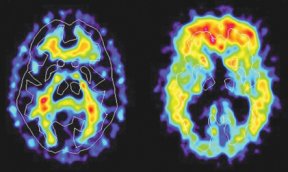

As minor forgetfulness progresses until names and faces blur, a person might be told that he or she probably has Alzheimer’s disease–but a definitive diagnosis awaits an autopsy showing the characteristic presence of beta-amyloid plaques clogging the brain. Now, researchers report that brain scans tracking a new compound can highlight these plaques in living people undergoing early stages of disease, when therapies may be most effective at staving off future memory loss.

In nine people with suspected early Alzheimer’s disease, brain scans lit up regions known to be plaque sites in the disease, Klunk says. In contrast, scans of five people in whom Alzheimer’s wasn’t suspected showed few signs of the marker. The findings were presented July 24 in Stockholm at the International Conference for Alzheimer’s Disease and Related Disorders.